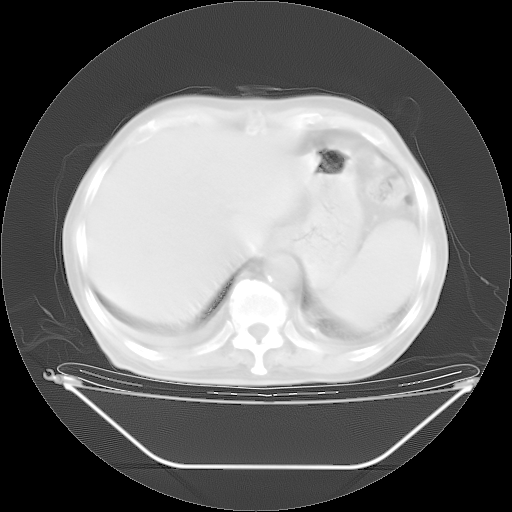

今天复查肺部CT,发现双肺广泛磨玻璃样改变。所以我把3月19日和5月9日相隔50天的肺部CT上传。请大家会诊。

5月9日肺部CT(在4月27日齐鲁医院肺部CT描述部分肺组织磨玻璃样改变,12天后肺组织广泛磨玻璃样改变)

大致读了系列胸部CT:纵隔窗无明显异常,肺窗:从4、27至今:主要是双肺中下野外带可见毛玻璃样改变,目前处于急性肺泡炎阶段,至于原因考虑1、结替组织或胶原血管性疾病所致?2、恶性疾病如恶组在肺部所致的表现或细支气管肺泡癌?3、药物或其它原因如肺蛋白沉着症所致肺泡炎目前不太可能?总之,明天就去请我院的呼吸科、感染科、血液科和临免专家会诊哈。